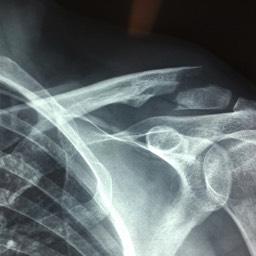

A 15 year old female fell from her pushbike causing a displaced left mid-shaft clavicular fracture. Seen 5 days later, plate & screws inserted 2 days later.

Image

DIsplaced fracture before surgery

DIsplaced fracture after surgery

Move the slider to compare before surgery and after surgery